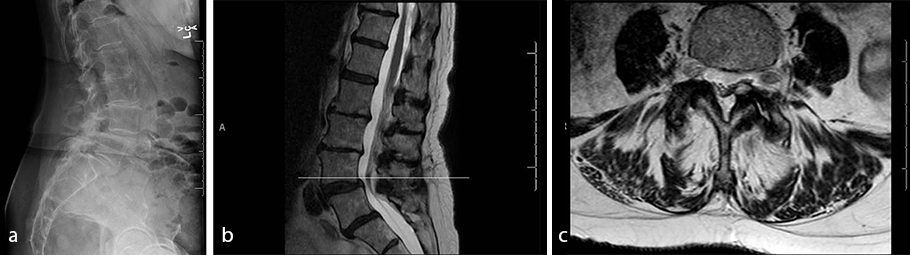

- A 73-year-old woman

- Severe and worsening low back pain, left lower extremity numbness, and radiculopathy

- Failed multiple rounds of conservative management including epidural steroid injections, physical therapy, and medications

- Imaging revealed L4/L5 spondylolisthesis and a left-sided synovial cyst (Fig 8)

- Diagnosis: lumbar spondylolisthesis and radiculopathy